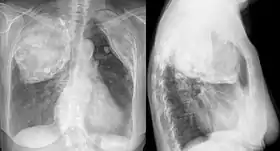

![]() X-ray in an elderly woman after pneumonolysis | |